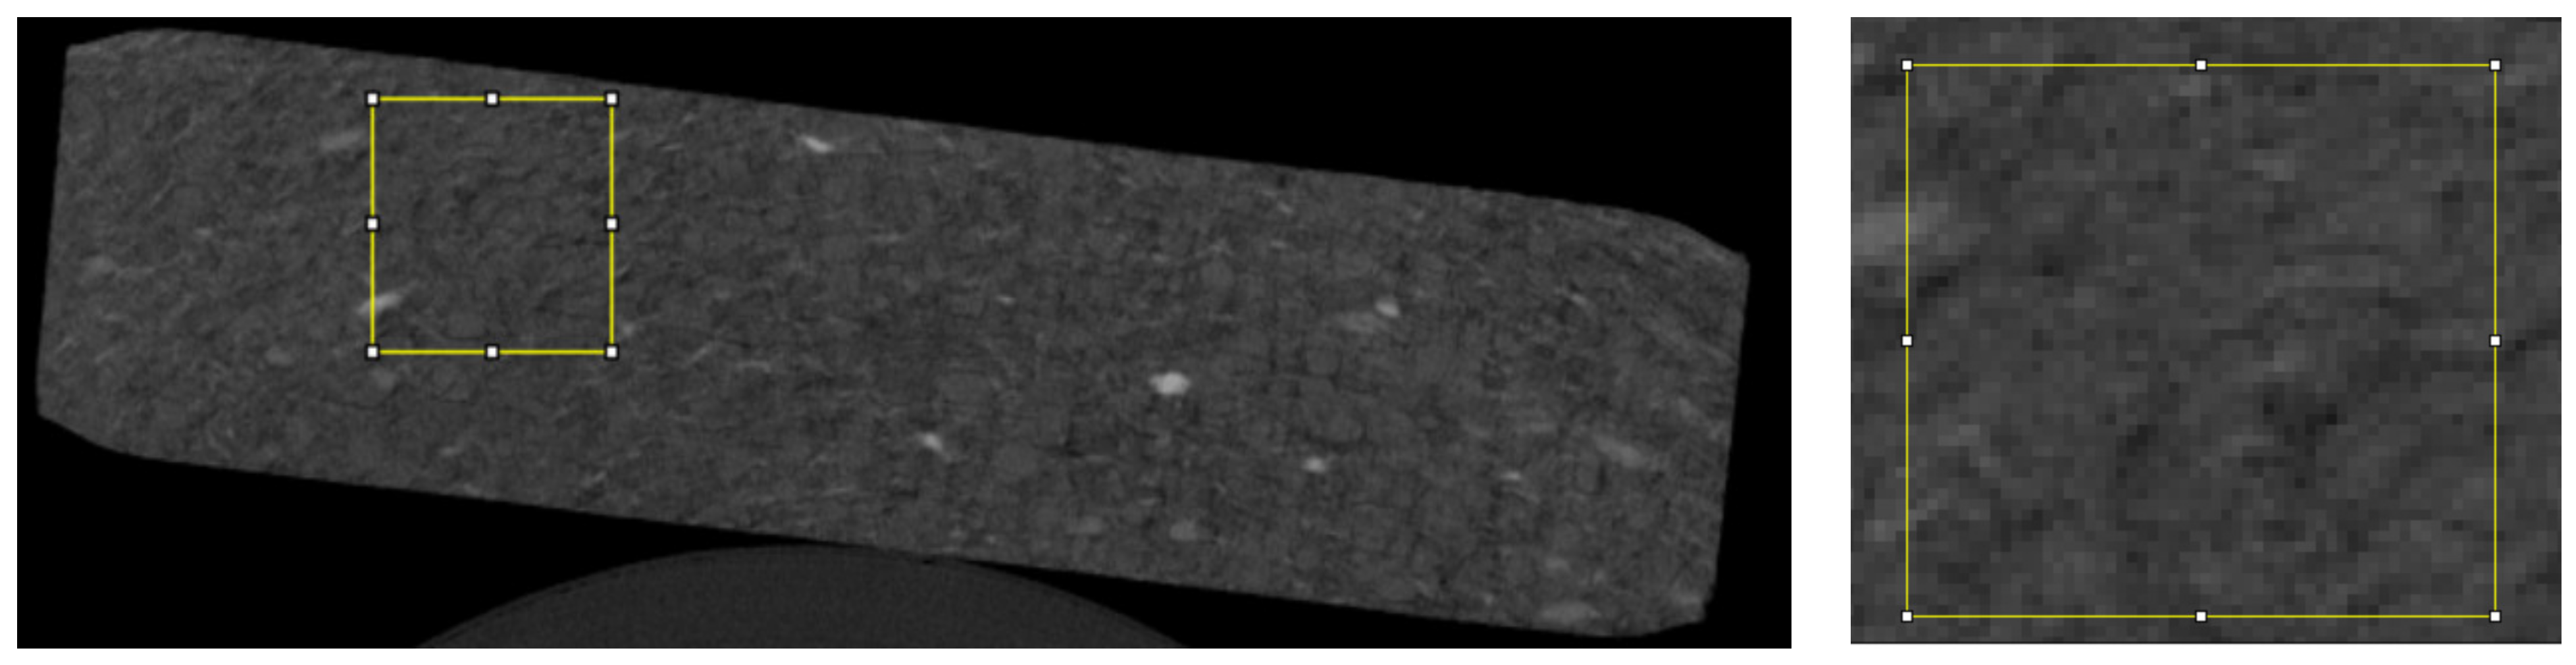

For the analysis, we used 20 randomly selected microtomographic slices of each type of tablet in which a total of 70 regions of interest (ROIs) were evaluated (Figure 1).

Figure 1.

The image shows an example ROI (yellow box) located throughout the tablet (on the left) and the ROI itself with visible pixels (on the right).